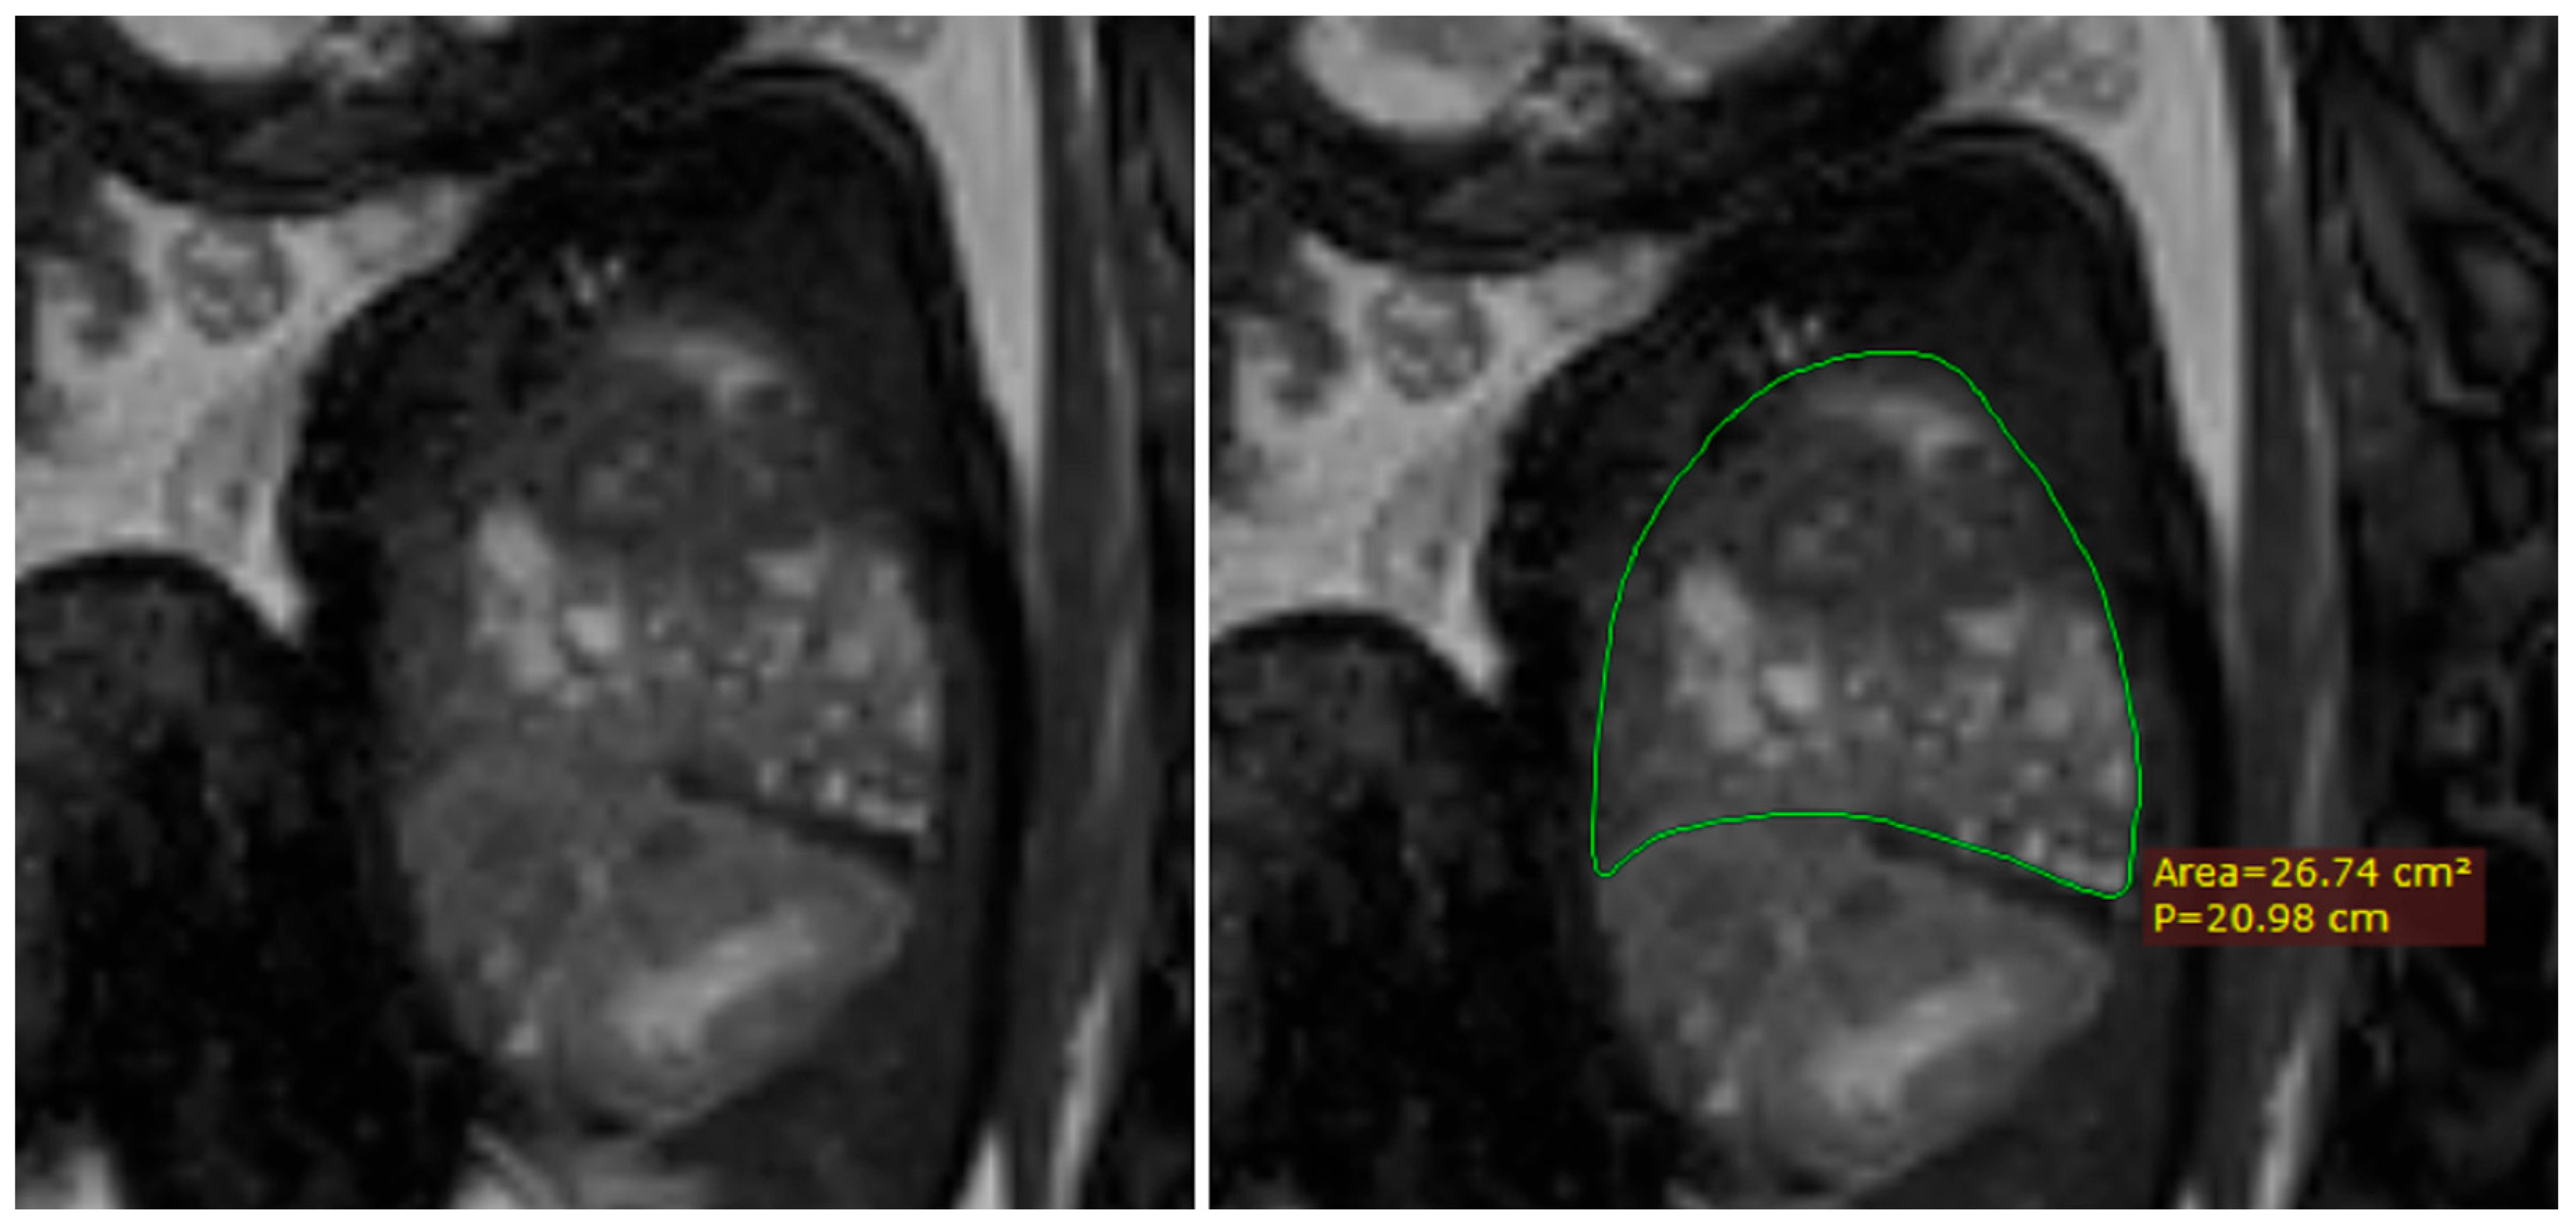

The thoracic circumference was measured following the outer margin of the ribs and respectively tracing the posterior contour of the vertebral transverse and spinous processes. Figure 5 and Figure 6.

The thoracic area, however, was measured on the interior margin of the ribs, the spinous processes, and the vertebral body. Figure 7 and Figure 8.

Furthermore, using the same method of calculating the lung volumes, we also measured the total thoracic cavity volume considering the upper margin of the thorax the superior thoracic aperture, and the lower margin of the diaphragm. This proved to be somewhat of a challenge when the herniation defect was larger, as the diaphragm was not so easily identified in some cases. Seeing as the diaphragm presented a loss of substance and continuity, we tried to identify the insertion of the diaphragm to the thoracic wall and trace an imaginary line that connected to its origin on the other side. This was best undertaken in sagittal images, but sometimes we found the coronal images to be better. Figure 9.

Figure 5. MRI axial T2 weighted image of the fetus showing how to measure the thoracic circumference, using the RadiAnt DICOM Viewer program, version number 2022.1.1. The green line represents the thoracic circumference.

Figure 7. MRI axial T2 weighted image of the fetus showing how to measure the thoracic area, using the RadiAnt DICOM Viewer program, version number 2022.1.1. The green line represents the thoracic area.

Figure 9. MRI sagittal T2 weighted image of the fetus showing the tracing method for calculating the thoracic volume, using the RadiAnt DICOM Viewer program, version number 2022.1.1. The green line represents the thoracic area on the herniated side. The p in the image stands for perimeter.